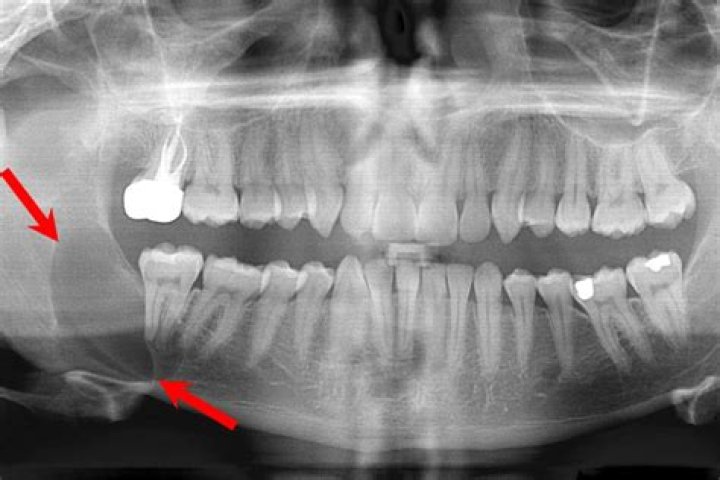

Can a tooth abscess cause tinnitus?

If your wisdom teeth are impacted or even infected, you may experience ringing in your ears as a result of their presence. Your ears may also ring if you have an abscessed tooth. Yes, it is possible for a tooth abscess to cause tinnitus

Ezoicreport this adIf your wisdom teeth are actually impacted, you may have a greater risk of developing an infection because of this. Infections can lead to inflammation, which in turn can cause hearing difficulties.

Teeth abscesses and impacted wisdom teeth have been linked to tinnitus. In these cases, additional dental work may be necessary to correct the problem. Tinnitus may go away on its own over time. One way this can happen is by aggravating an already-existing TMJ disorder.